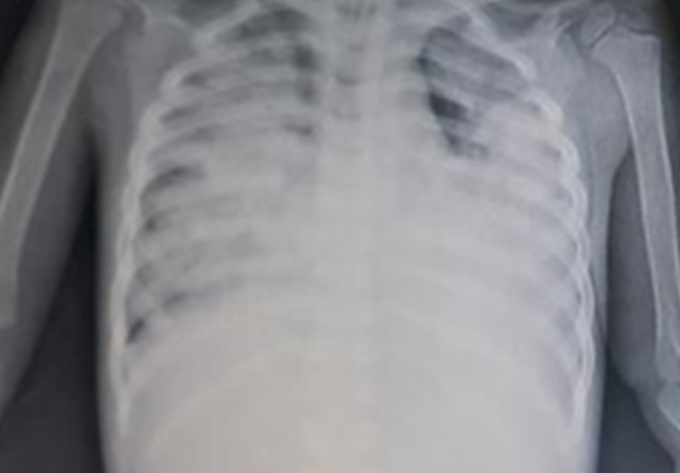

Sau đó, bệnh nhi hô hấp diễn tiến xấu hơn, hình ảnh X-quang phổi cho thấy tổn thương phổi nặng lan tỏa 2 bên, biểu hiện hội chứng suy hô hấp cấp tiến triển nặng nên được các bác sĩ hội chẩn toàn viện, quyết định thực hiện kỹ thuật oxy hóa máu qua màng ngoài cơ thể (ECMO), là vũ khí, phương tiện hỗ trợ hô hấp cuối cùng cho những trường hợp suy hô hấp nguy kịch. Bên cạnh đó, bệnh nhi cũng được điều trị hỗ trợ gan, điều chỉnh nước điện giải, toan chuyển hóa, kháng sinh, hạ sốt, dinh dưỡng.